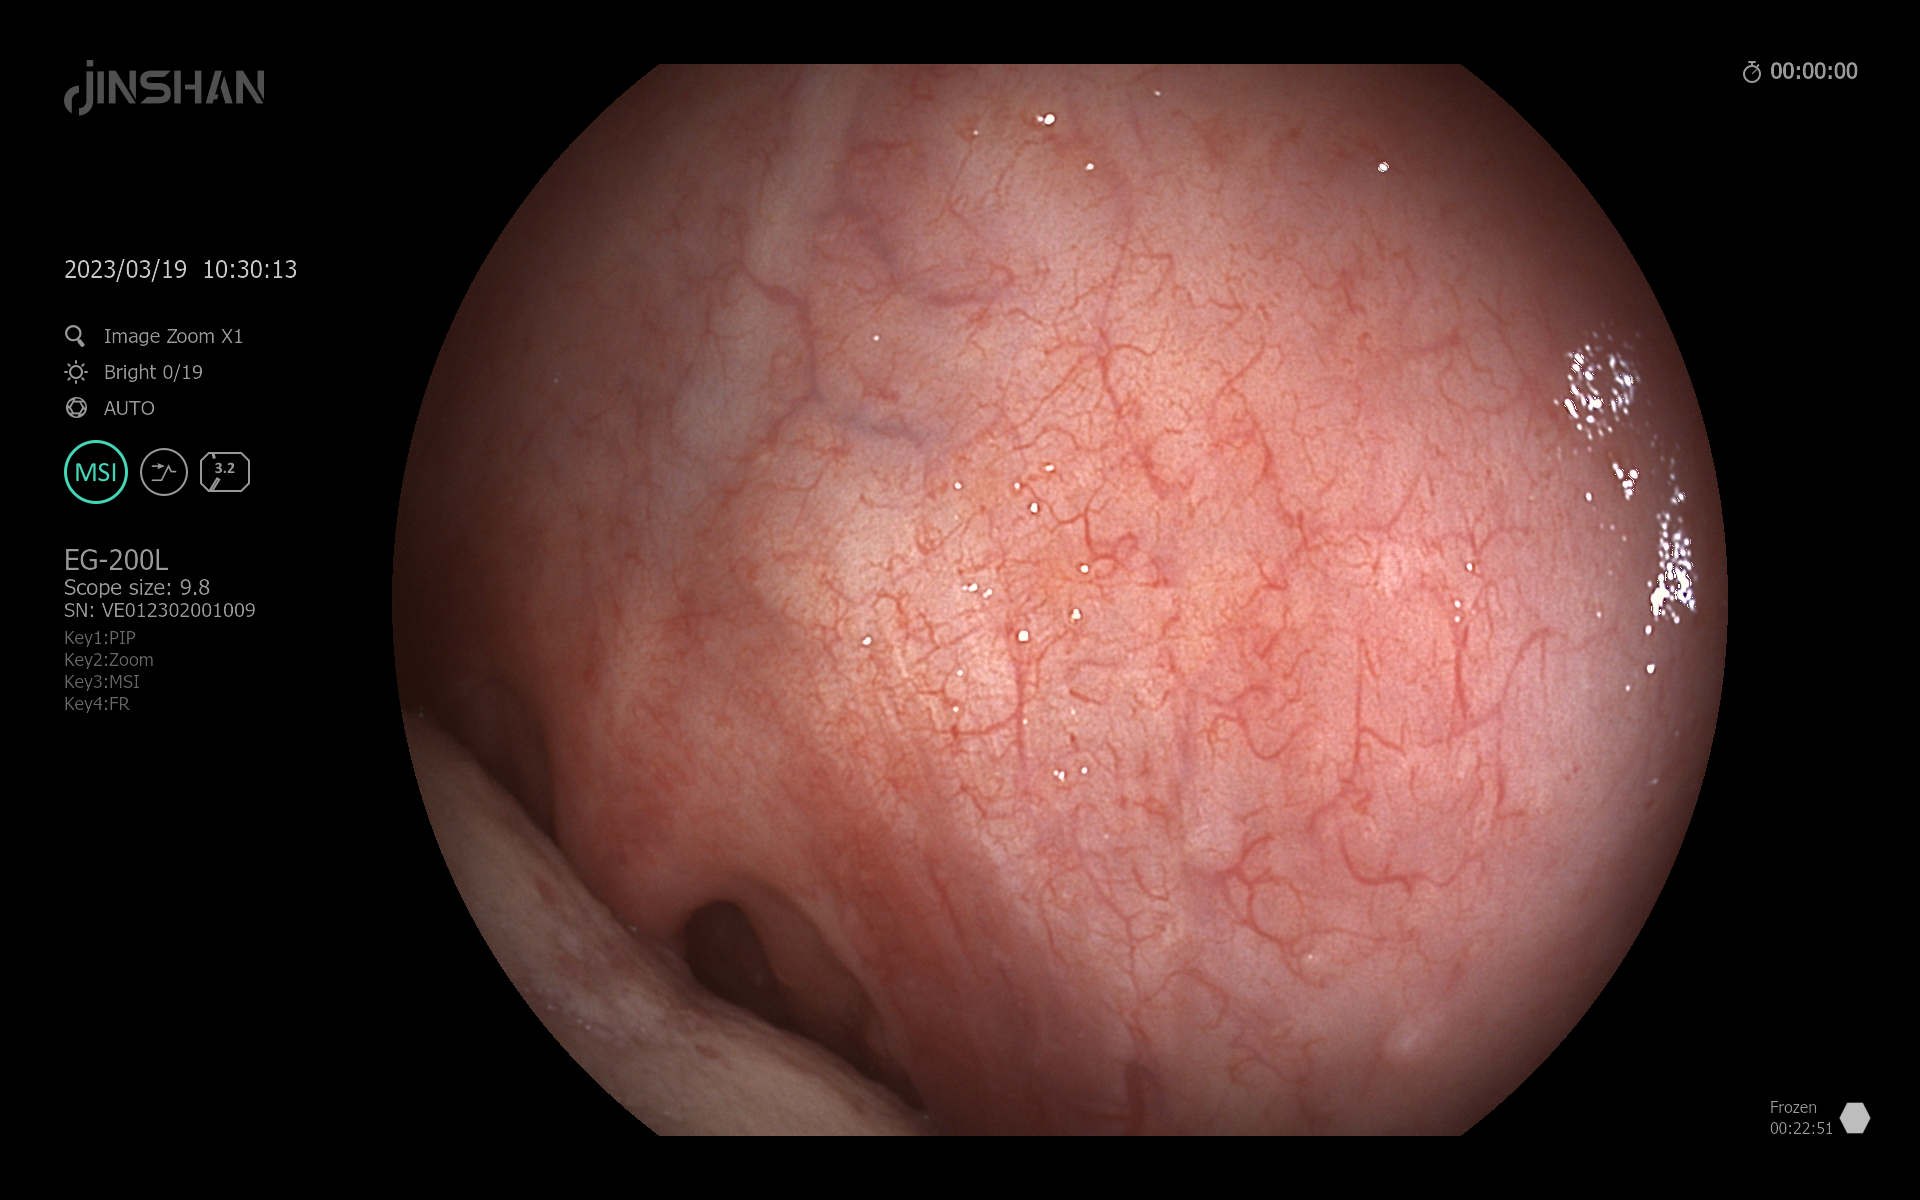

By analyzing the pixels at the corresponding location, the video data is the same, and figures 1 and 2 are visualizations of fpga.bin and arm.bin respectively, which are no different from the visual effects. But the difference is clear when the data on the arm side is sent to the display:

Figure 1

Figure 2